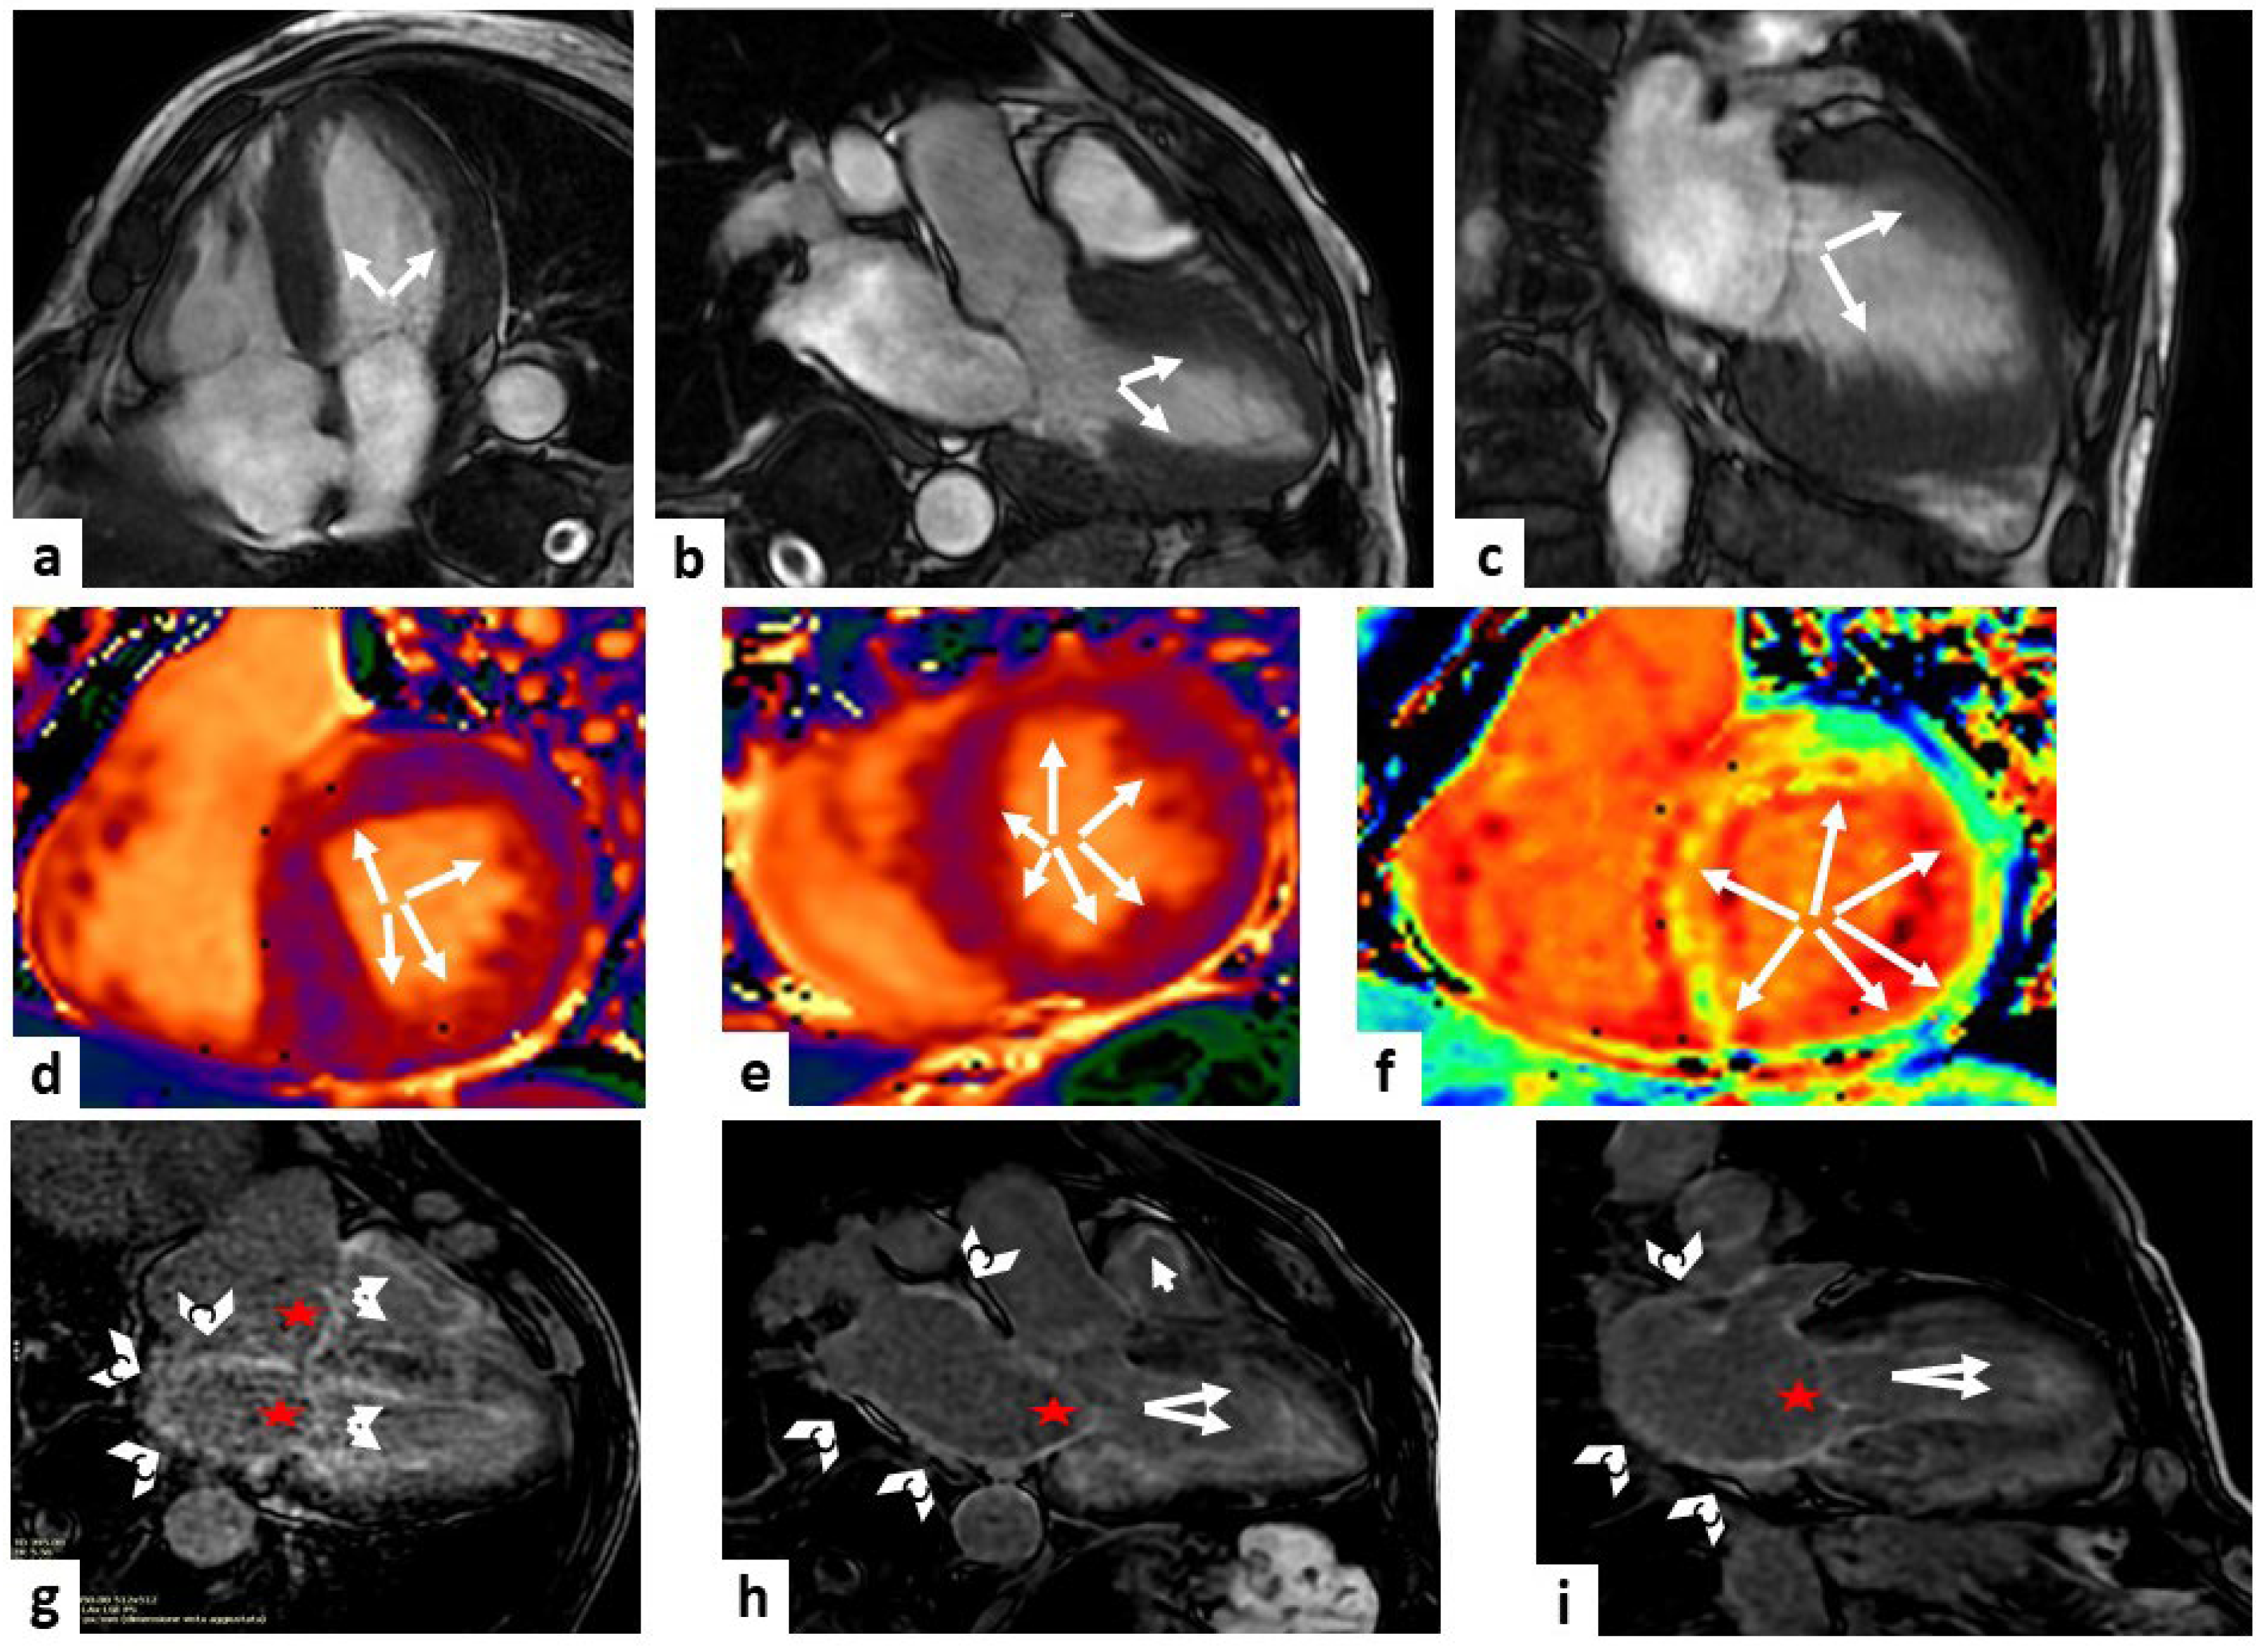

Postcontrast T1 mapping, which can be incorporated into standard LGE-CMR protocols, is useful to compute an ECV increase caused by amyloid infiltration (Figure 2). Recent studies demonstrated that high levels of ECV (ECV > 0.40%) can help to diagnose CA early on and are a prognostic sign in both ATTR and AL amyloidosis [56,57].

Figure 2.

Cardiac amyloidosis. A case of a 79-year-old man, with magnetic resonance imaging (MRI) showing a hypertrophic (white arrows) left ventricle (LV) of 17 mm in the steady-state free precession (SSFP) sequences (panels (a–c) show four-chamber, three-chamber, and two-chamber views, respectively). Mid panels show diffuse high values at T1 mapping sequences, represented by the orange tonality as indicated by the white arrows (panels (d,e) at the level of the basal and mid-LV short-axis views, respectively) and diffuse high values at extracellular volume (ECV) sequence, represented by the yellow tonality as indicated by the white arrows (panel (f) at the level of the basal LV short-axis view). Late gadolinium enhancement (LGE) sequences showed a non-ischemic enhancement pattern in both ventricles (white arrows), a hyperenhancement of the atrio-ventricular valves (red stars), of the left atrium wall and the interatrial septum (white arrowheads) (panels (g–i) show four-chamber, three-chamber, and two-chamber views, respectively). All these findings are diagnostic of cardiac amyloidosis.

T2 mapping is a noncontrast sequence and, as compared to T1 mapping, is more specific to detect myocardial oedema. T2 mapping values are increased in patients with both forms of CA, with a greater prevalence in AL than in ATTR.